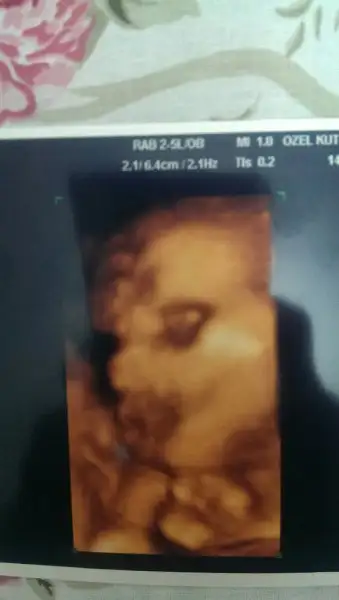

Evet canım. Ikiz bebek ölçümlerinde değiller. Sağdaki 3 hafta önde. Soldaki 2 hafta önde. Dr böyle giderse 3 kiloyu geçer dedi. Normal de ikiz bebekler 1.500-2500 kg arasında doğarlarmış. 2500 kg nimet gözüyle bakıyorlar. Dr kilo aldırmaya uğraşma dedi halbuki ben bütün gün açım. Hem istifra ediyorum hem de midem hep sıkışık halde 2 lokmada doyuyorum. Hala sıfır kilo ile devam ediyorum. Bebekler alıyor ben zayıflıyorum. Yüzüm çöktü resmen. Taşıma konusuna gelince işimiz çok zor. Ağrılarım var. Dr masajla rahatlayabilirsin dedi. Çünkü magnezyum yetmiyormuş